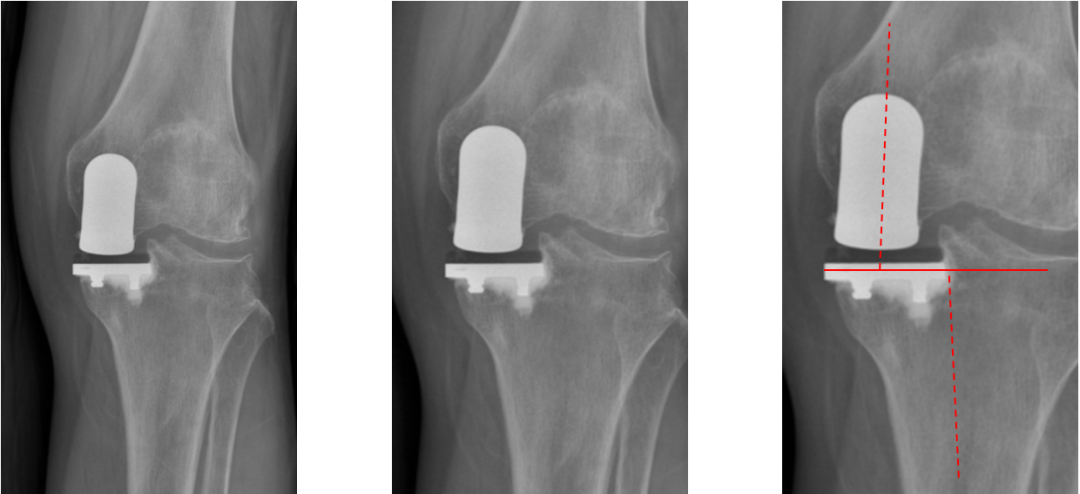

标准胫骨假体位置

AP位胫骨与股骨假体位置:水平截骨与胫骨轴线垂直,无明显内外翻,内侧缘与胫骨平台内侧缘齐平; 股骨假体中线与胫骨假体中线一致。

标准胫骨假体位置(KA)

AP位胫骨与股骨假体位置:水平截骨与胫骨轴线 3°内翻截骨,内侧缘与胫骨平台内侧缘齐平; 股骨假体中轴线与胫骨假体垂直,股骨假体中线与胫骨假体中线一致。

胫骨假体内翻

AP位胫骨与股骨假体位置:胫骨假体内翻10°,股骨假体中轴线与胫骨假体垂直。